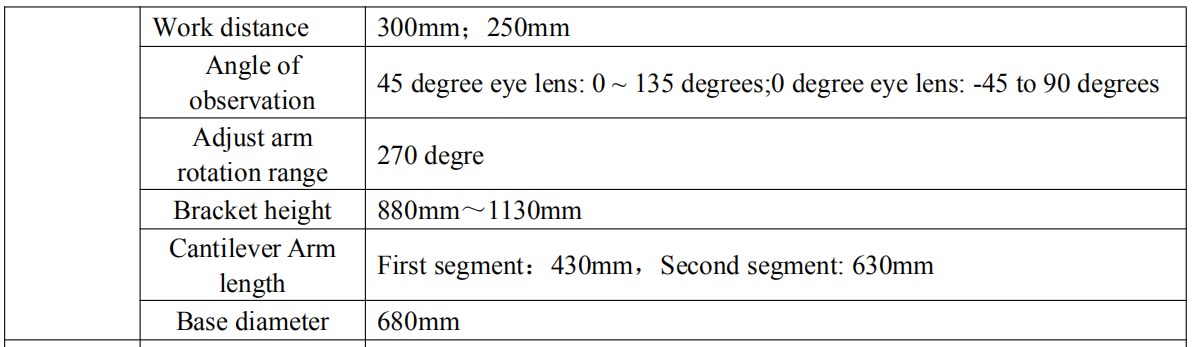

Binocular eyepiece technical parameter